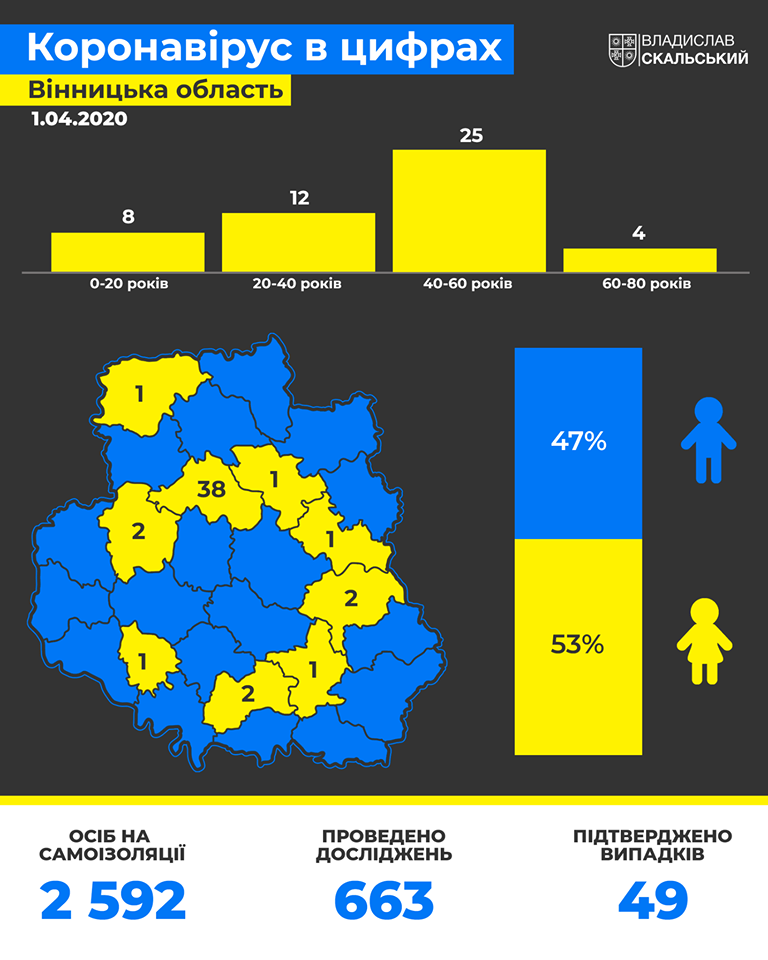

Зазначимо, що станом на сьогодні на території Вінницької області зафіксовано вже 49 випадків інфікування Covid-19. Хворих виявлено у восьми районах області, найбільше їх наразі в обласному центрі.

Як зазначається в інфографіці, опублікованій на сторінці голови ОДА, станом на сьогодні найбільше на території області хворіють люди віком від 40 до 60 років (25 осіб), також серед хворих більше жінок, ніж чоловіків.